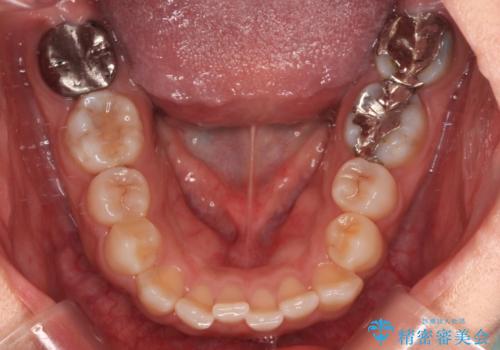

- 上下前歯の叢生を気にして来院された患者様です。

軽度な叢生であり、安価で短期間の治療を規模されていたため、インビザライン・モデレートを用いて矯正治療を行うこととしました。